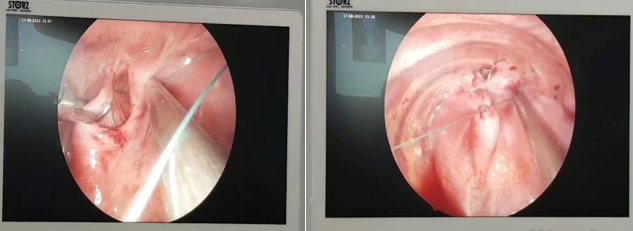

Hình ảnh lỗ thoát vị cơ hoành trước và sau khâu tạo hình

Trong quá trình phẫu thuật, theo ghi nhận của Bác sĩ trẻ bị thoát vị hoành bên trái, qua lỗ thoát vị lớn, nhiều quai ruột non, đại tràng ngang theo lỗ thoát vị lên khoang lồng ngực làm nhu mô phổi trái xẹp, kíp phẫu thuật đã tiến hành phẫu thuật trả các tạng thoát vị về ổ bụng và thực hiện khâu phục hồi cơ hoành trái cho trẻ. Ca phẫu thuật diễn ra trong vòng khoảng hơn 30 phút đã thành công tốt đẹp, giúp trẻ thoát khỏi tình trạng nguy hiểm tính mạng. Ngay sau phẫu thuật gần 1 giờ trẻ đã phục hồi sinh hoạt bình thường, bú mẹ tốt, hết tình trạng nôn và khó thở.